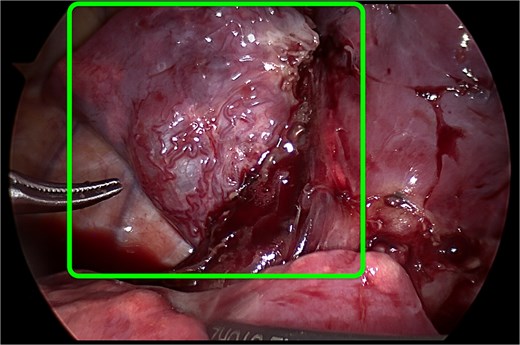

All patients underwent elective thoracoscopic lower lobectomy at a mean age of 18.3 months (range 16–21 months). Procedures were performed under general anesthesia with selective single-lung ventilation. The thoracoscopic approach included three ports placed under direct visualization. Careful dissection was performed to identify and ligate the segmental pulmonary artery branches, pulmonary veins, and bronchus of the affected lobe (Fig. 2). The specimen was retrieved in an endoscopic bag, hemostasis was verified, and a chest drain was placed in all cases. No conversions to thoracotomy were required. Mean operative time was 110 minutes (range 95–135 minutes). There were no intraoperative complications.

Thoracoscopic view of the CPAM in the lower lobe of the right lung. The malformation is highlighted by the green contour.